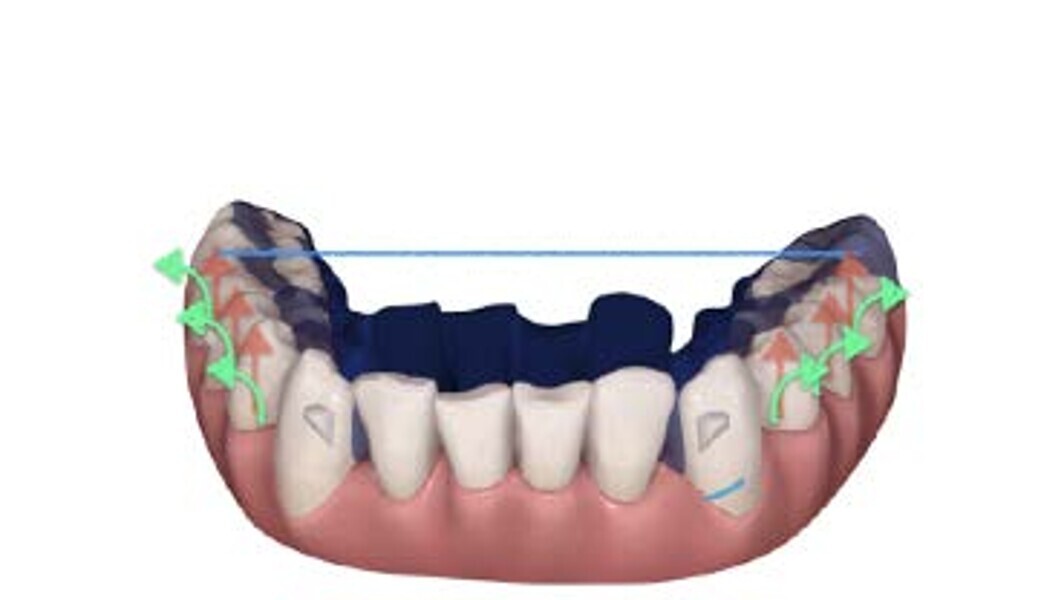

To properly correct deep bite malocclusion with aligners, the Invisalign system (Align Technology) has introduced precision bite ramps, anterior customised bite turbos, embedded into the aligners, and these are available for the lingual surface of the maxillary central and lateral incisors or of the maxillary canines. This feature does not require composite filling like for traditional attachments; it is a lingual extension of the aligner (maximum palatal extension of 3 mm) that creates premature anterior contacts and posterior disocclusion. The ramps are planned to move, stage by stage, in a more occlusal direction, creating the necessary posterior occlusal space to permit lateral and posterior teeth to extrude relatively. The ramps need to be combined with two other features: extrusion attachments on lateral teeth and mandibular incisor pressure areas, a lingual pressure point designed to exert intrusive forces following the long axis of the incisors more effectively. In this way, the levelling of the mandibular curve of Spee will be more reliable, combining two reciprocal movements in two different parts of the arch, anterior intrusion, and posterior extrusion, as indicated in the literature (Figs. 1–8).6, 7

When planning the digital set-up (ClinCheck software), careful levelling of the curve of Spee in 3D needs to be addressed, in particular:

On the vertical plane, the mandibular second molars represent a reference point, so they do not need to be extruded, whereas extrusion should be planned for the first molars, second premolars and (sometimes) first premolars (depending on the severity of the curve). The intrusion should be achieved simultaneously from canine to canine, creating a normal overbite.8

On the sagittal plane, distal tipping of the second and first molars will support the curve of Spee levelling, in combination with reciprocal mesial tipping of premolars and canines. This movement is synergic, and distal tipping will favourably partially extrude the molars.

On the transverse plane, the uprighting of premolars and molars reaching a torque close to 0° will create a relative extrusion of the lateral segments, contributing to the levelling of the curve of Spee and premature posterior occlusal contacts.9

This amount of posterior extrusion planned in 3D will create, on the digital plan, heavy occlusal contacts on the working cusps, and these premature contacts will lead to proper intercuspation clinically, without losing the occlusal contacts during treatment, generating mandibular clockwise rotation. Finally, to favour mandibular rotation and proper intercuspation, Class II elastics with a vertical component of force directly connected to the aligners will be helpful for achieving true and relative extrusion.